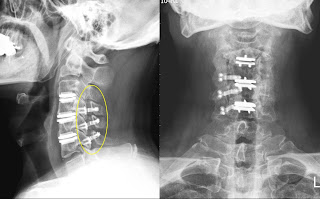

| 術後病人脊椎裝置了三節的人工椎間盤 |

許先生看我似乎有疑惑欲言又止的樣子,便很直接地說:「鄞醫師,不瞞您說, 我本身就是一位醫師, 這次手術也是經由同學介紹去找某醫院的名醫開的,光人工椎間盤的費用就花了超過70萬,費用對我是小問題, 但我覺得手術後反而更嚴重, 糟糕的是後來醫師說目前很難再處理;這三年我遍訪北中南的名醫,也託人介紹, 但其他醫師看到我的狀況以及X光,都不太願意接手,這簡直宣判我沒救了;我還沒發病的時候可是運動健將, 你看到我現在還能走路,其實是靠意志力硬練復健來的......」